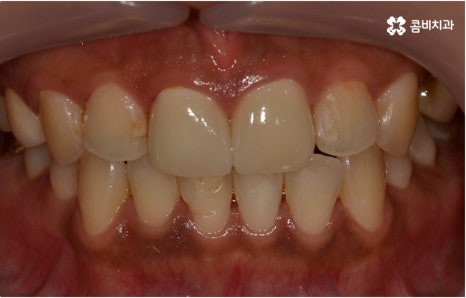

저작 기능 뿐 아니라 치아는 말을 할 때 분명한 발음을 할 수 있도록 해 주는 조음 기관이며, 턱관절과 함께 얼굴 윤곽, 즉 하관을 잡아주는 역할도 하기 때문에 심미적인 균형 면에서도 중요한 역할을 하고 있어요. 대인 관계에서 자신감이나 태도를 결정하는 데에도 영향을 주고 있기 때문에 심리적인 중요성도 크다고 할 수 있습니다. 그렇다면 이렇게 중요한 치아, 치아를 받쳐주는 잇몸, 위아래 교합과 관련된 턱관절 등 모든 부분을 종합적으로 생각했을 때 구강 건강을 지키는 방법은 무엇일까요?

관리의 측면에서 교합이 맞지 않고 치열이 똑바르지 않으면 음식물 찌꺼기가 잘 끼고 잇몸이 붓기 쉽기 때문에 교정 치료가 필요할 수도 있습니다. 씹기가 어렵고 안면비대칭이나 턱관절 통증을 유발하는 등 심각한 부정교합의 경우 기능적으로도 필요하지만 약간 삐뚤어지거나 치아 사이가 벌어진 경우 심미적으로도 한 번쯤 교정 치료를 생각해 보셨을 텐데요, 가격이나 기간, 나이 등 여러 가지 부분이 신경쓰여서 막상 시작하기에 부감을 느끼고 계셨다면 먼저 명동치과 에 내원하셔서 자신에게 필요한 교정 치료가 어떤 것인지 알아보시면 좋을 거예요. 골격적인 원인이 크지 않고 정도가 심하지 않다면 환자분들의 상황에 따라 부분 교정으로 보다 짧고 간편하게 진행하는 경우도 있으니 3D CT 와 같이 정밀 검진 기계를 갖춘 치과에서 숙련된 의료진에게 검진 및 상담부터 받아보시길 권유드리고 있습니다.